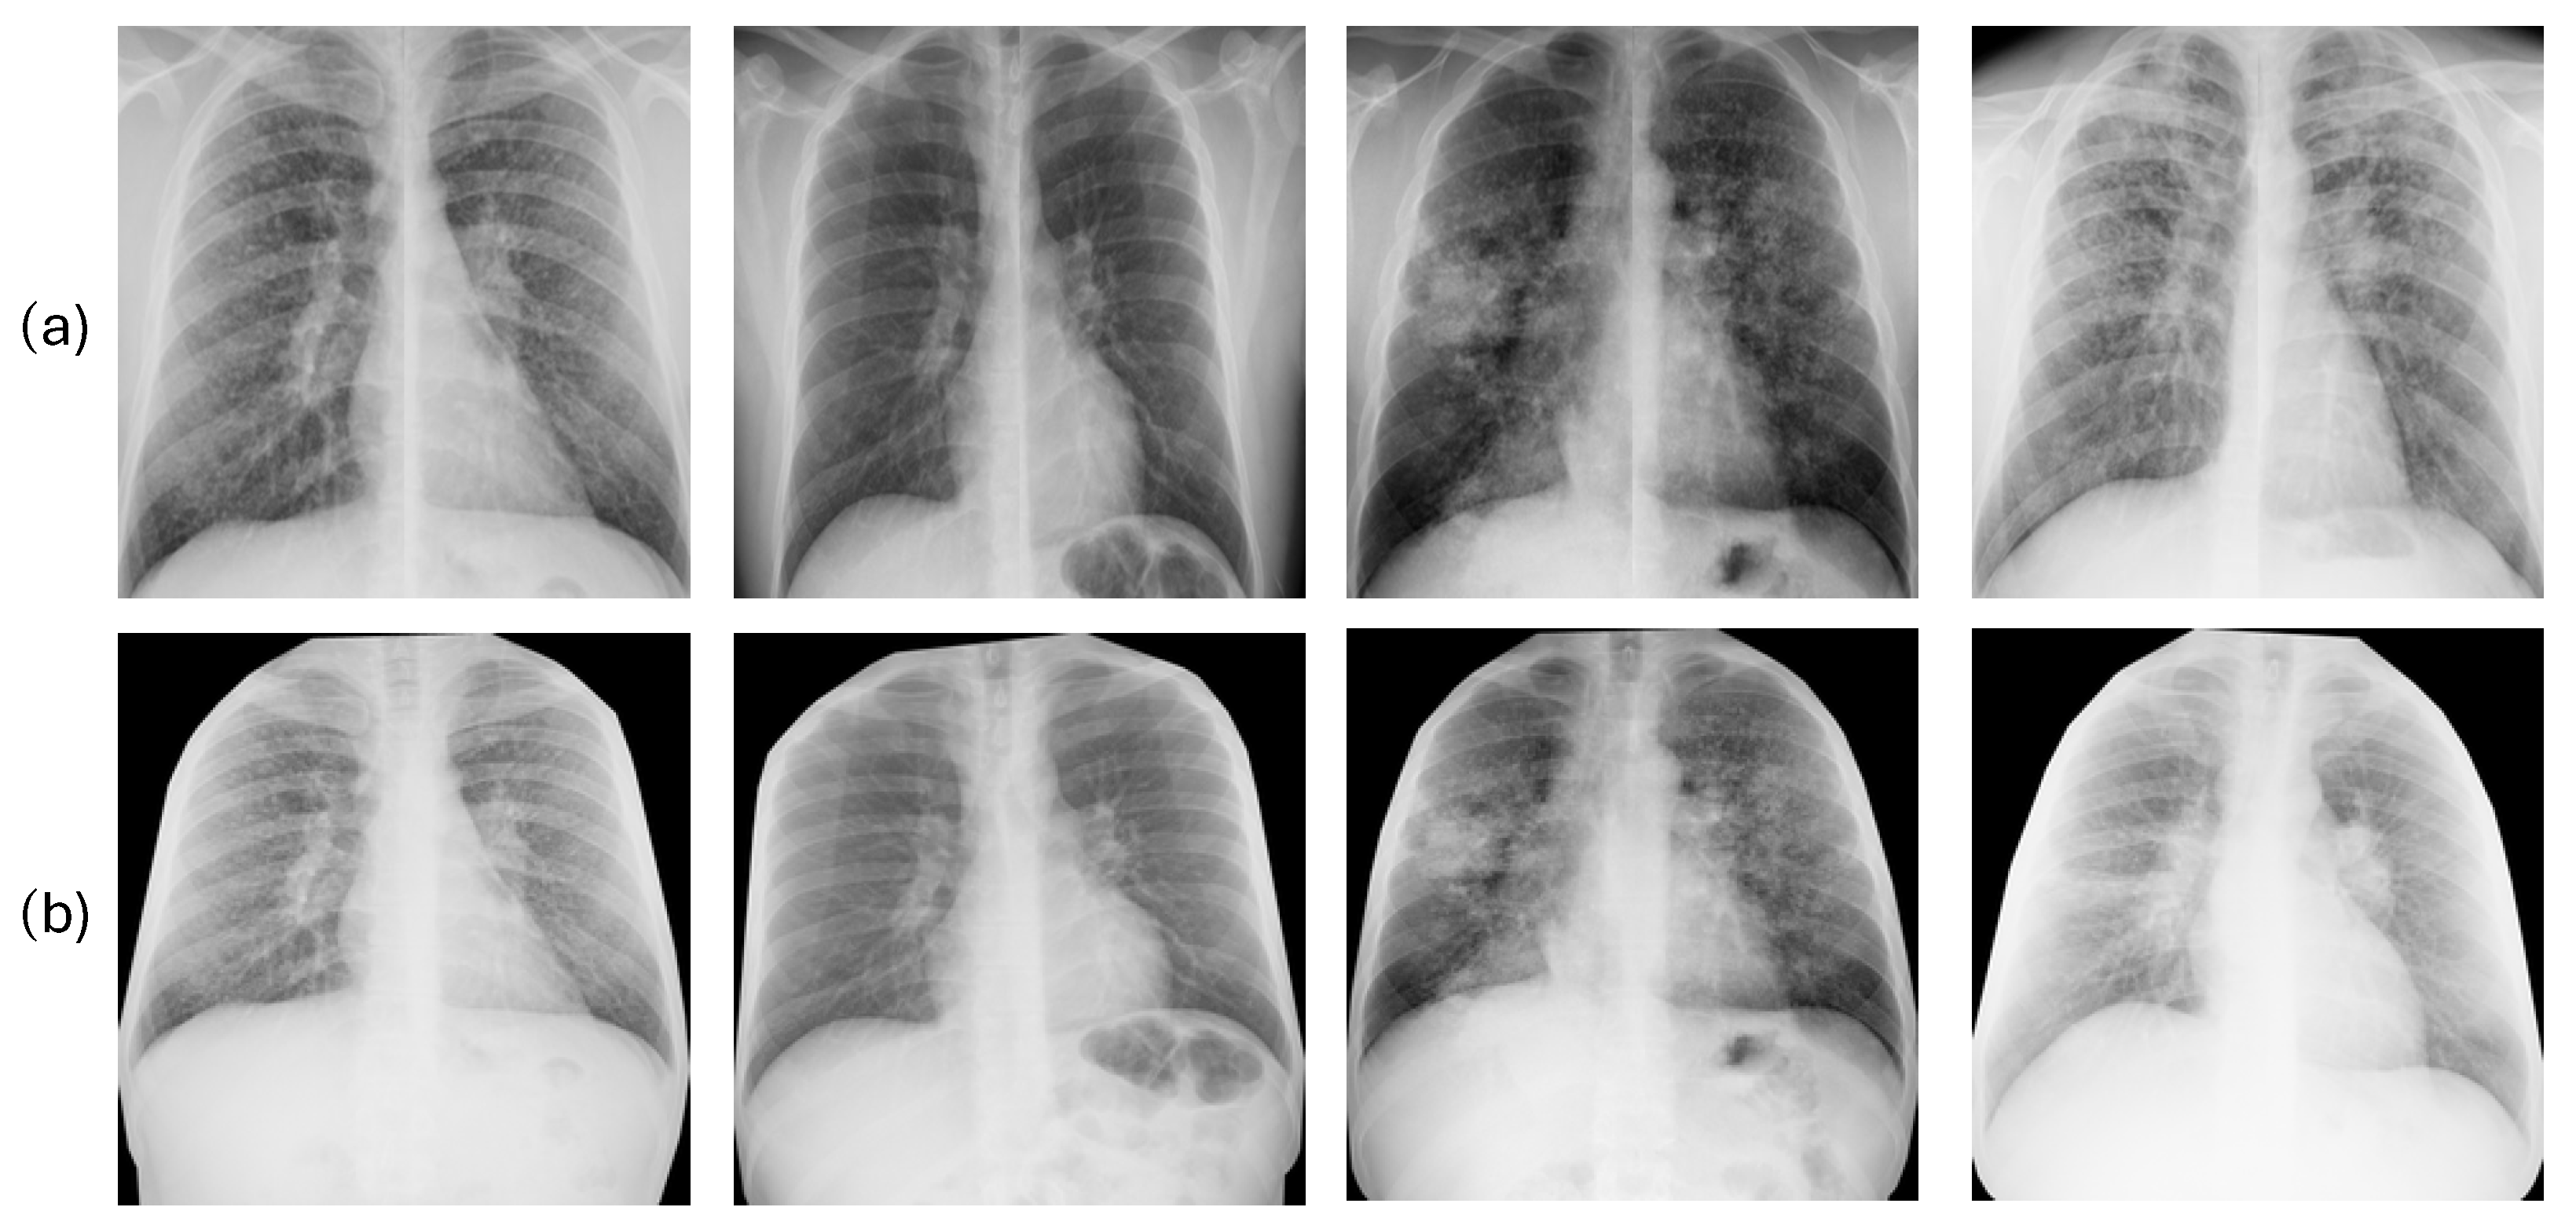

2.7.1. Image Preprocessing